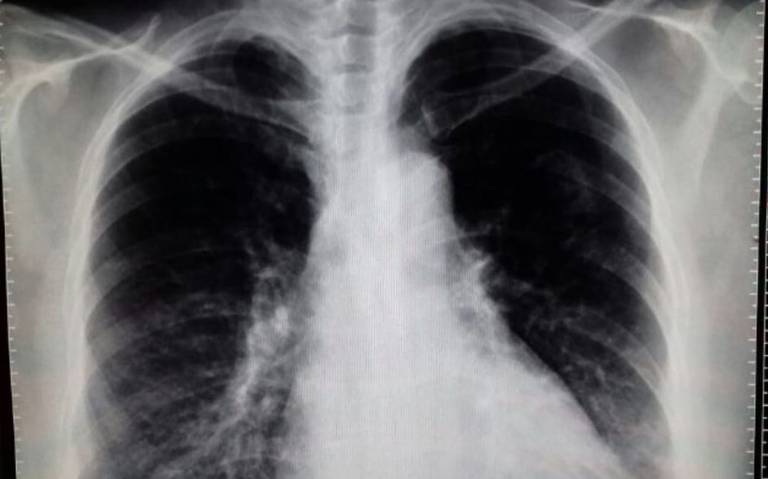

Corticosteroides en la neumonía bacteriana adquirida en la comunidad: una revisión sistemática, metanálisis por pares y dosis-respuesta

La evidencia de certeza moderada indica que los corticosteroides reducen la mortalidad en pacientes con neumonía bacteriana adquirida en la comunidad más grave, la necesidad de ventilación mecánica invasiva y el ingreso en la Unidad de Cuidados Intensivos. J Gen Intern Med 19 de abril de 2023